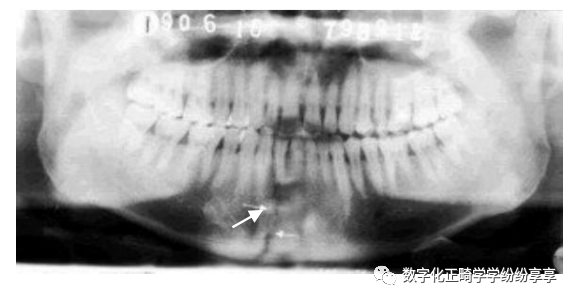

骨折问题:

颏部骨折

曲面断层片怎么看正畸【曲面断层片(全景片)】如何解读和查看:牙周?牙体?牙髓?关节?_https://www.jmylbn.com_新闻资讯_第24张

颏孔区骨折

曲面断层片怎么看正畸【曲面断层片(全景片)】如何解读和查看:牙周?牙体?牙髓?关节?_https://www.jmylbn.com_新闻资讯_第25张